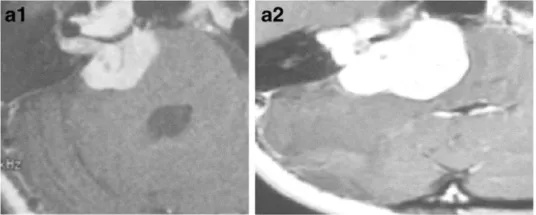

一名29岁女子初期出现身体不平衡和不稳定。核磁共振成像显示右侧有一个30毫米的病灶,有实性和囊性成分(图2a)。患者在诊断后立即接受了放疗。8个月后进行的随访MRI显示肿瘤的实性部分轻微增加,但囊性部分扩大(图2b)。她接受了立体定向囊肿穿刺引流,没有明显好转。在接下来的随访期内,肿瘤和囊肿继续增大,患者因不平衡恶化而变聋,且只能坐在轮椅上。患者随后接受了显微外科手术切除肿瘤经迷路的方法。由于肿瘤包膜和脑干之间存在严重粘连,因此进行了次全切(图2c)。手术后,面神经功能正常,病人好转到行走状态。

图2:29岁女性。a增强后轴向核磁共振显示右侧中等大小的肿瘤,不均匀强化压迫脑干。肿瘤具有实体和囊肿部分(在直线加速器治疗之前)。b增强后轴向MRI显示肿瘤实体部分轻微生长,囊性部分增大(直线加速器治疗后8个月)。肿瘤缺乏中央强化。c术后增强轴向MRI显示肿瘤的一小部分残留